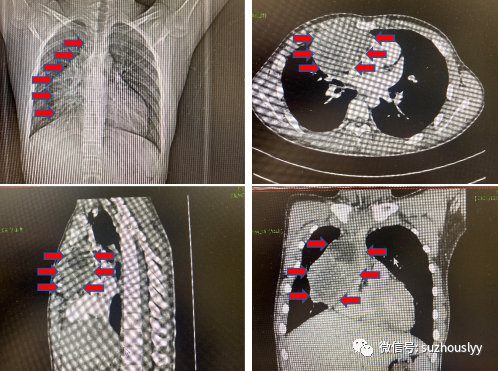

患者,男性,15岁,一场突来的不适,使这位朝气蓬勃的少年备受打击。2021年7月出现胸部疼痛不适,伴胸闷气短,伴发热,体温最高达39℃,本以为只是普通感冒发烧,但输液治疗数天后症状逐渐加重,并有明显的呼吸困难。患者胸部CT提示:纵隔肿瘤,重度胸腔积液。病理结果提示:生殖细胞肿瘤,考虑为卵黄囊瘤。卵黄囊瘤为高度恶性肿瘤,这无疑给15岁的孩子宣判了死刑。父母为了孩子的一线生机,四处奔走求医未果。2022年1月入住我院心脏大血管外科,张学勤主任接诊后非常重视,随即完善全身检查,充分了解患者病史、家庭情况及患者相关历次检查后,组织科内全体医护人员开展病例讨论和治疗方案,充分评估了术中及术后可能出现的各种手术风险。由于该病发病率低,恶性程度高,国内外相关诊疗经验缺乏,而且该患者肿瘤较大,侵犯肺组织、心包、右心房、上腔静脉、无名静脉。尤其是右侧肺门处,肿瘤与右肺动静脉及支气管关系密切,考虑完整瘤体切除存在极大困难,同时该肿瘤生长速度快,瘤体血运丰富,肺门处如无法完整切除可能出现术中大量出血,严重危及患者生命安全的状况发生张主任在与国内知名业内专家多次讨论。最终确定了手术方案,决定行纵隔恶性肿瘤扩大切除术(瘤体切除+心包切除+部分肺组织)。同时,备用体外循环或上腔静脉、无名静脉—右心房转流术,为手术安全顺利的进行提供保障。手术台上,张学勤博士在麻醉科和手术室的默契配合下,成功完成该患者纵隔恶性肿瘤扩大切除术(包含完整瘤体、部分心包、部分肺组织、部分膈肌组织、纵隔胸腺组织、右侧隔神经部分切除吻合),成功将肿瘤从上腔静脉、无名静脉等重要脏器组织剥离,避免了使用体外循环、血管置换。此举加速患者术后恢复,确保肿瘤术后远期预后良好。历时5个小时,手术顺利完成,总失血量约200ml,术后见标本大小约12*9*8厘米。